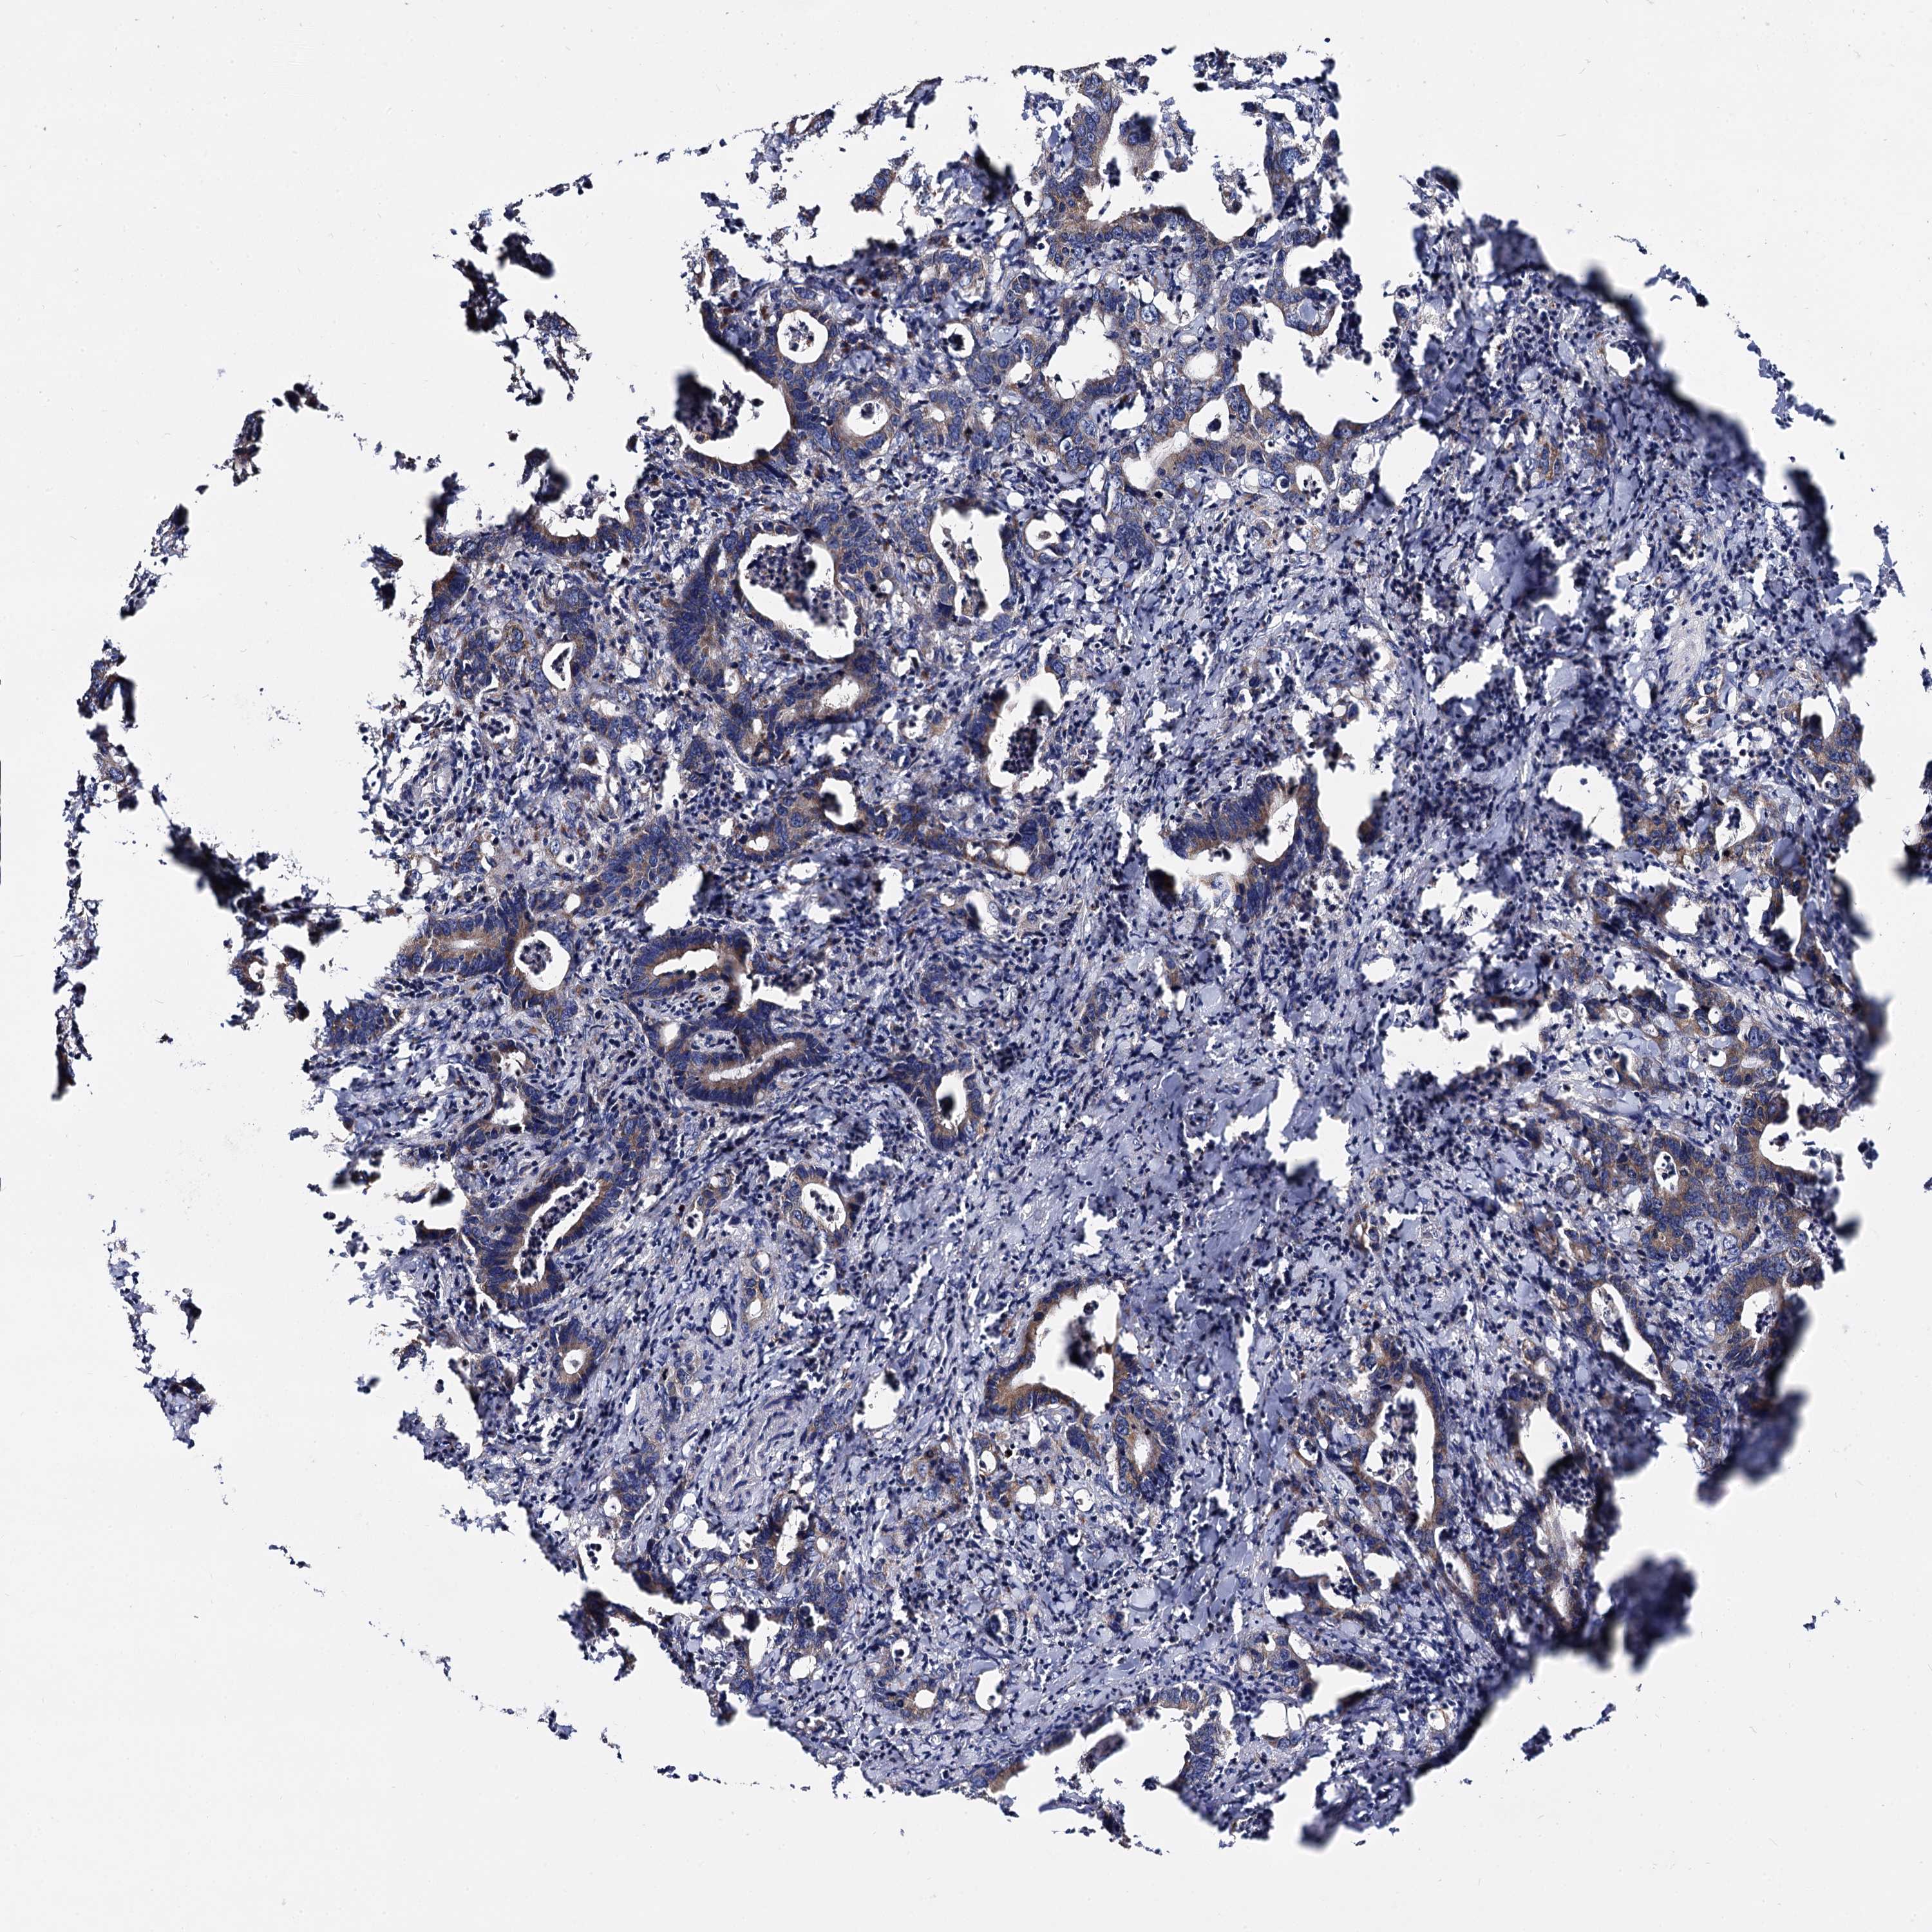

CANCER COLORECTAL CANCER Show tissue menu

Colorectal cancer

Human cancer

Colon adenocarcinoma